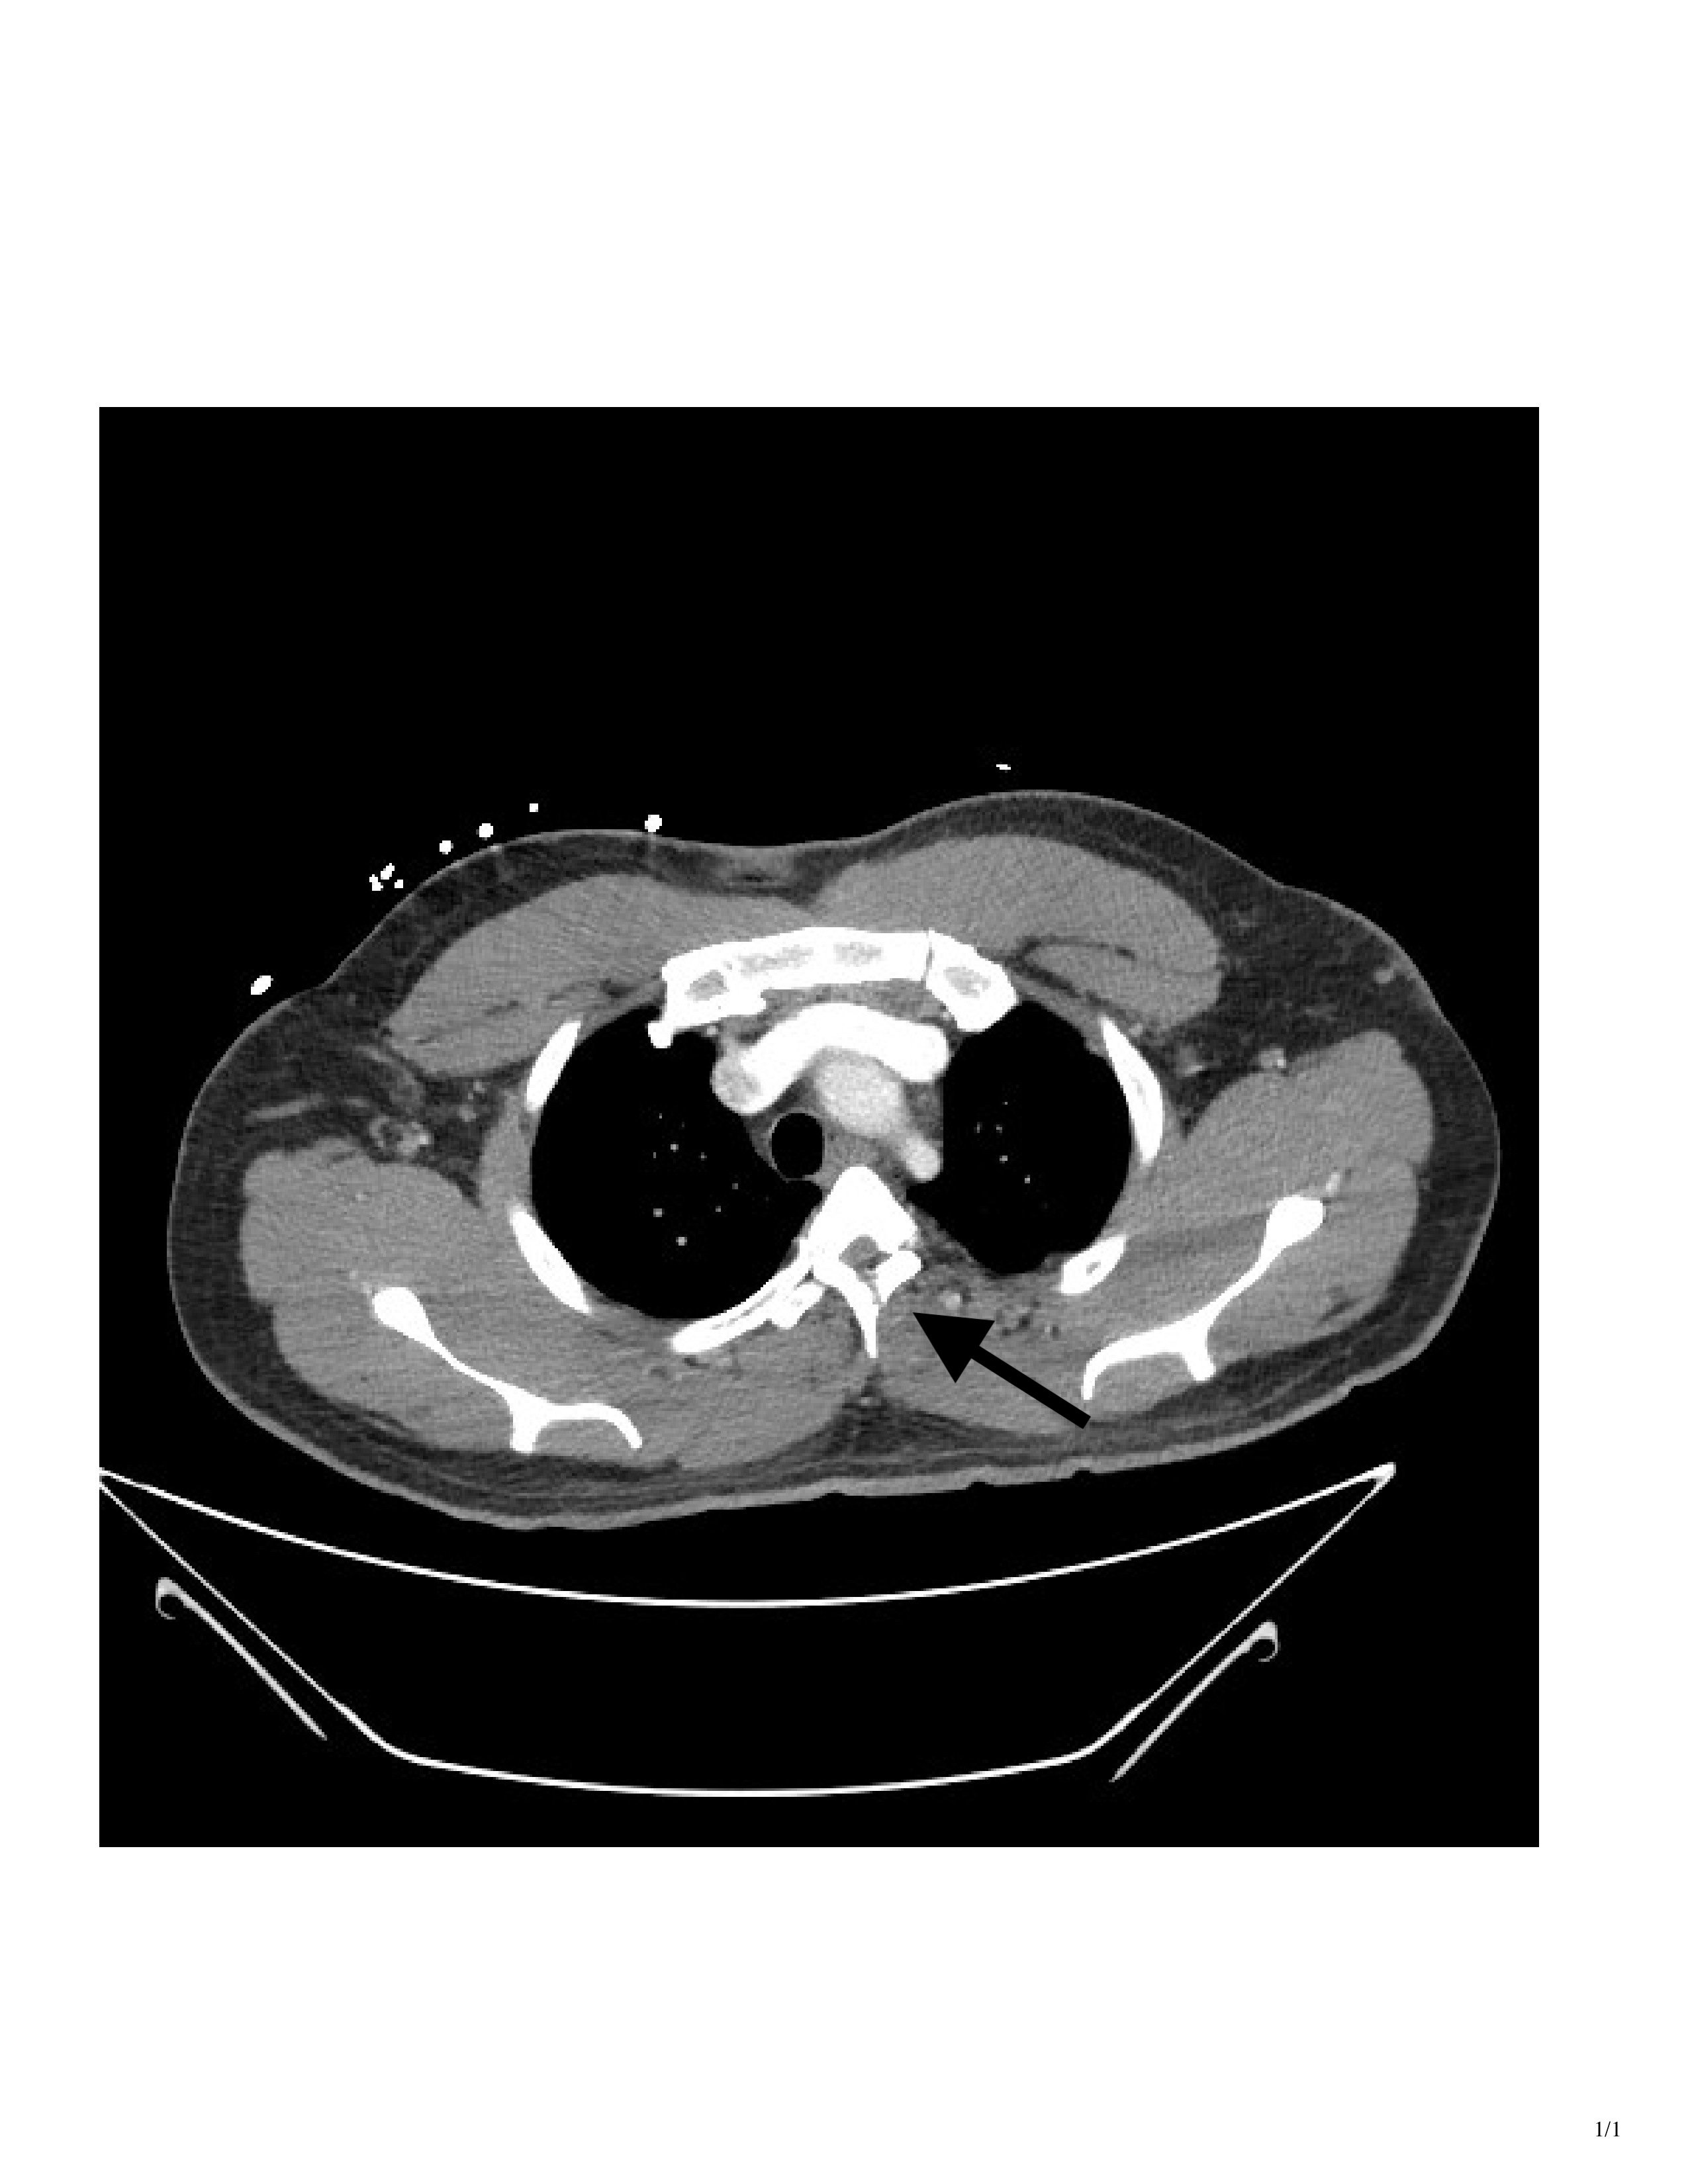

CT imaging showed a T3 spinous process fracture raising concern for intracanal blood products and possible cord injury. MRI later that night confirmed cord contusion with possible injury to the right hemi cord, and dorsal epidural hematoma extending from T2 to T10.

At the time of presentation, we knew the patient displayed clinical signs of Brown-Séquard, and the CT showed injury on the right side of the cord. What was unclear at the time was whether the patient had a true hemi-section of the spinal cord, leading to permanent disability, or if he was instead suffering from a transitory spinal shock due to swelling and hematoma.

An MRI obtained the next day confirmed right-sided spinal cord hemi-section, as well as associated cord contusion and epidural hematoma. Additionally, when the patient was discharged from the Shock Trauma ICU several days later, he was still exhibiting the same neurological deficits. The patient was discharged directly to a rehabilitation center, where occupational and physical therapists were expected to help him maximize his recovery and learn to live with his new deficits.